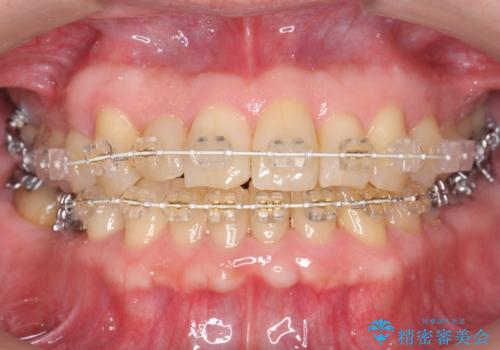

50代男性 受け口 他院で5年以上かかると治療を断られた

- 50代男性

- 矯正装置

- 審美装置

- 治療期間

- 3年6ヶ月

- 受け口を主訴に来院。

他院での矯正相談は、5年以上かかると言われ、やんわりお断りされたとのことでした。

ずっと矯正はしたかったがあきらめていて、50代で退職を機に新しいことを初めて、歯並びも諦めずに治したいとのことでした。顎の手術は避け、歯の移動だけでの治療をご希望されていました。

ある程度時間はかかることは説明させていただき、治療開始しました。

右上の八重歯は、右上の奥歯を矯正用ミニスクリューを用いて遠心移動を行い解消しました。

下の前歯はIPR(エナメル質を薄く削り歯を小さくする処置)を行なっています。